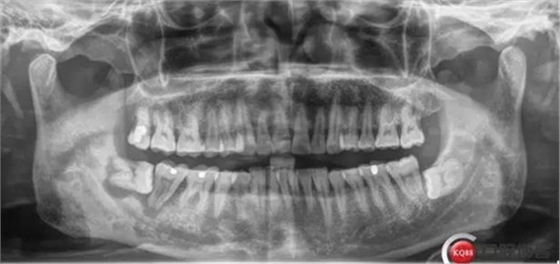

口內(nèi)檢查:47 II度松動(dòng),48未完全萌出,II度松動(dòng),探針牙齦出血,有膿液,叩診(+),口腔衛(wèi)生條件較差。

X線及CBCT檢查:47、48根尖周區(qū)大面積低密度影像,波及下牙槽神經(jīng)管,部分區(qū)域至神經(jīng)管以下。CBCT顯示神經(jīng)管走形于47根尖炎癥區(qū)下方(已侵犯)48炎癥區(qū)頰側(cè)(已侵犯)